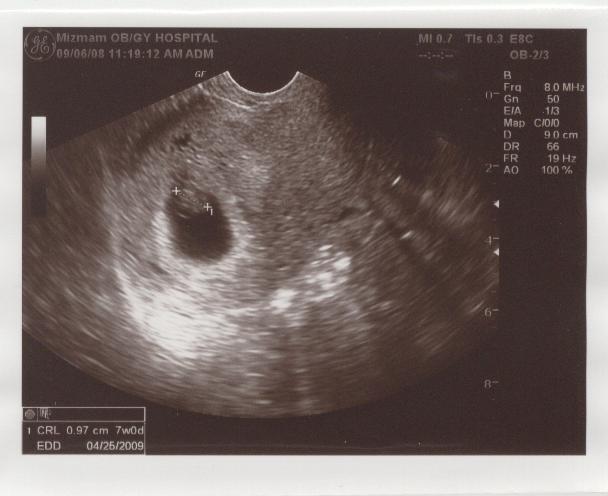

우리 아기 별 - 초음파사진02-7주 01.jpg

첫째 아이 초음파 사진